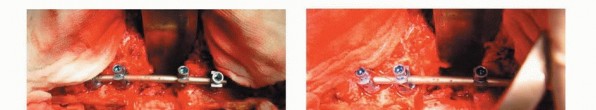

4. Dissection of the Spinal Cord and En Bloc Corpectomy

Using a cord spatula, the spinal cord (dura mater) is mobilized from the surrounding venous plexus and the ligamentous tissue. T-saws are inserted at the proximal and distal cutting levels of the vertebral bodies after confirmation of the disc levels with needles. Recently, a diamond T-saw is now available for corpectomy. The teeth-cord protector, which has teeth on both edges to prevent the T-saw from slipping, is then applied. The anterior column of the vertebra is cut by the T-saw, together with the anterior and posterior longitudinal ligaments(TECH FIG 5). The freed anterior column is rotated around the spinal cord and removed carefully to avoid injury to the spinal cord. With this procedure, a complete anterior and posterior decompression of the spinal cord (circumspinal decompression) and total en bloc resection of the vertebral tumor are achieved.

TECH FIG 5. A. A temporary posterior instrumentation is performed to maintain stability after segmental resection of the anterior column. B,C. The anterior column of the vertebra is cut by the T-saw, together with the anterior and posterior longitudinal ligaments. The teeth-cord protector, which has teeth on both edges to prevent the T-saw from slipping, is then applied. (continued...)

TECH FIG 5. (continued...) D. Schematic drawing of cutting the anterior column. E. Diagram of en bloc corpectomy. F. Intraoperative photograph of specimen from the resected T7 vertebra. G. Specimens resected along with the compartment and barrier concept. H,I. Radiographs of resected specimens from metastatic tumor of T7 showing the complete vertebra in horizontal (H) and lateral (I) views.